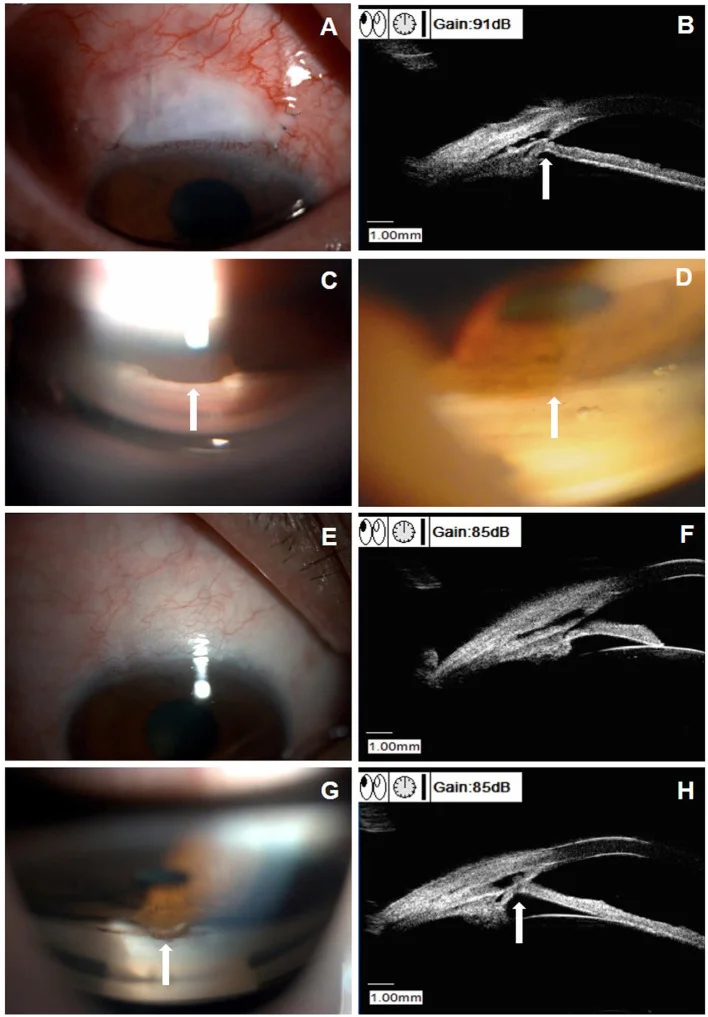

プラトー虹彩症候群による再閉塞:LPI開通後も散瞳時に隅角閉塞が発生しうる7)。41歳女性でLPI開通にもかかわらず散瞳後に急性隅角閉塞を生じ、最終的に線維柱帯切除術+白内障手術を要した症例が報告されている7)。UBMによるプラトー虹彩の評価が重要である7)。